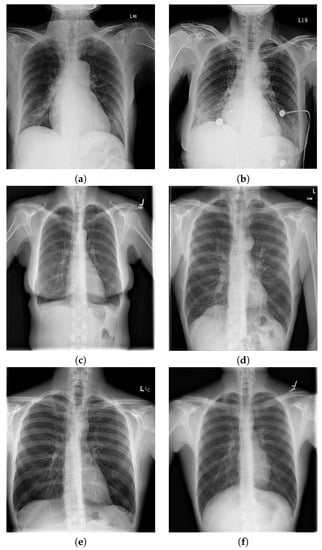

Images used in this analysis came from anteroposterior radiographs (X-rays). Radiography is a technique for generating and recording an X-ray pattern to provide the user with a static image(s) after the end of X-ray exposure, as displayed in Figure 12. The erect anteroposterior (AP) chest view is performed with an X-ray tube firing photons through the patient to form the image on a detector positioned behind the patient [].

Figure 12.

Example of X-rays: (a,b) coronavirus (COVID-19); (c,d) other diseases; and (e,f) healthy. Source: prepared by the authors.

An exploratory analysis of the metadata provided by the COVID-19 Image Data Collection resulted in the data shown by Figure 13. Such metadata information was used in our predictive models since it is only available for COVID-19 cases. In addition, statistics metrics from patients’ ages and sex information were calculated: mean = 59.45, median , and standard deviation = 16.88. Figure 12 displays an example of a healthy chest X-ray and an X-ray of a patient diagnosed with COVID-19. These images correspond to the dataset used to train our models. No data augmentation process was used.